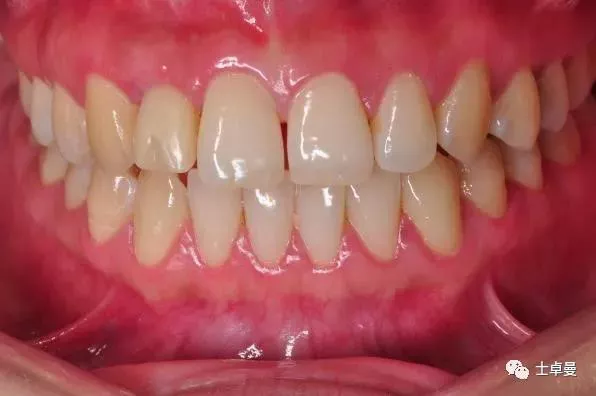

口内完成修复当日

完成修复一年后复查

修复后3年复查

患者微笑照